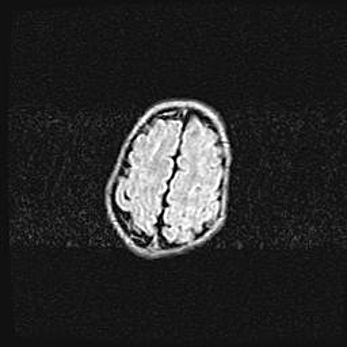

Лейкомаляция с кистозно-глиозной дегенерацией головного мозга.

Возраст: 2 месяца 25 дней

Вес: 6400 г

Окружность головы: 40 см

Срок гестации: 41 неделя

Лейкомаляцию относят к ишемически-гипоксическим повреждениям головного мозга, диагностируемым у новорожденных. При лейкомаляции в головном мозге обнаруживают очаги некроза, возникшие после тяжелой гипоксии и нарушения кровотока. В процессе морфогенеза очаги проходят три стадии: 1) развития некроза, 2) резорбции и 3) формирования глиозного рубца или кисты. Перивентрикулярная лейкомаляция (ПЛ) встречается примерно в 12% случаев среди новорожденных, обычно – у недоношенных детей, причем, частота ее зависит от массы, с которой младенец появился на свет. Наибольшее число малышей страдает лейкомаляцией, если масса при рождении 1500-2500 г.